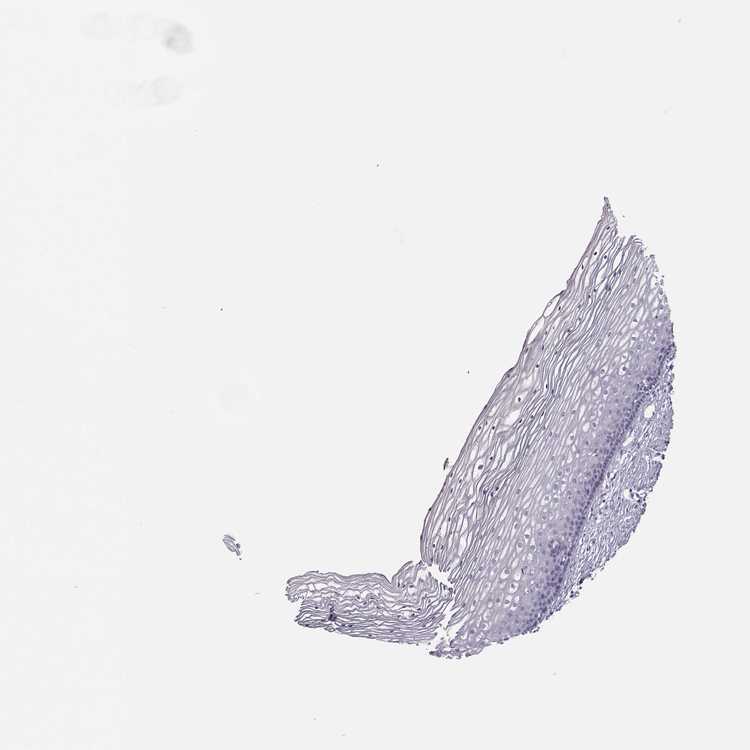

CERVIX - Antibody stainingi

Antibody staining in the annotated cell types in the current human tissue is reported as not detected, low, medium, or high, based on conventional immunohistochemistry profiling in selected tissues. This score is based on the combination of the staining intensity and fraction of stained cells.

Each image is clickable and will lead to virtual microscopy that enables deeper exploration of all samples and also displays staining intensity scores, fraction scores and subcellular localization as well as patient and tissue information for each sample.

Antibody HPA055162

Squamous epithelial cells Not detected